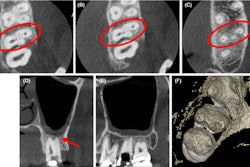

CBCT shows the (A) six root canals of tooth #16 and three mesiobuccal root canals, (B) two palatal root canals of tooth #17, and (C) two distobuccal root canals of tooth #17.During root canal preparation, they could see that two of the canals in the mesiobuccal root of tooth #17 were joined together. The canals in the palatal roots were separated in the middle of the palatal root and met together in the third apical. X-rays and an electronic apex locator were used to determine the roots' working lengths. The preparation was completed, and the access cavity was sealed with temporary filling.